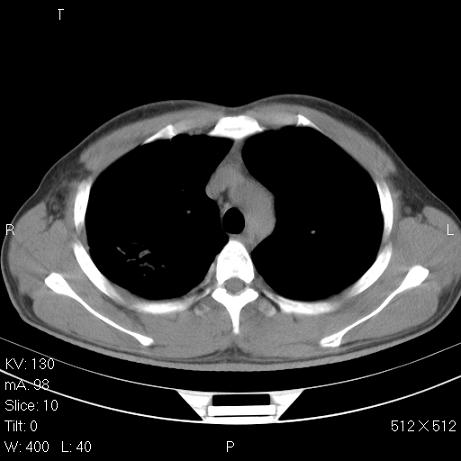

标题: CT7171B:补充治疗后2周复查

治疗后2周复查,请讨论

结合以前的ct片,还是考虑肺挫伤,吸收多了。

支持:创伤性湿肺。现肺挫裂伤(出血 积气)大部分吸收。建议继续治疗!

支持:创伤性湿肺、肺挫裂伤。现肺挫裂伤(出血、渗出、液气腔)大部分吸收。建议继续治疗!

经治疗后病灶明显吸收,考虑创伤性湿肺、肺挫裂伤